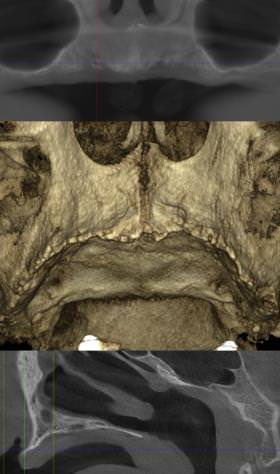

Danes se večina dela opravi izven operacijske dvorane. Pacientom napravimo rentgenske posnetke s stožčastim snopom (CB CT) in nato skupaj s strokovnjakom, ki obvlada delo s programsko opremo za načrtovanje izdelave subperiostalnih vsadkov, načrtujemo obliko in pozicijo teh vsadkov.

Te vsadke, ki se jih izdela iz titanijevih zlitin, se na kost pričvrsti s posebnimi titanijevimi vijaki in to na tistih mestih obraznega skeleta, kjer je za to dovolj kosti. Gre za kratke vijake dolžine od 3 do 7 mm. Poseg se izvede v splošnem opoju popolnoma brez bolečin – pacient je v napol budnem stanju, za kar skrbi anesteziolog, ki je prisoten ves čas operacije. Takoj po operaciji se odvzame odtis za izdelavo proteze, ki jo pacienti prejmejo dan, dva ali tri dni kasneje, odvisno od tega, ali je pred izdelavo potrebna še kontrola. Gre za začasno protezo, ki se jo po šestih mesecih zamenja s stalno. Najkasneje nekaj dni po posegu imajo torej pacienti izdelano protezo s katero lahko uživajo hrano in je izdelana po grebenu čeljustnic, nebo pa je prosto, hkrati pa takšna proteza še vedno nudi dobro podporo ustnicam, kar je pomembno iz estetskega vidika.